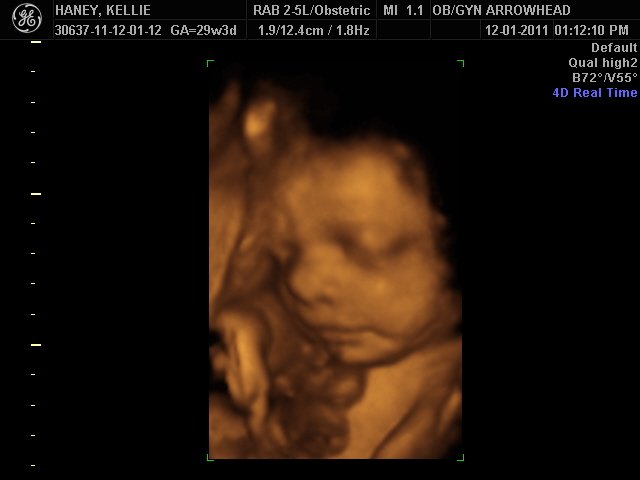

We offer complimentary 3D/4D Ultrasounds to all our OB patients around 30 weeks! The following photos are some examples of our work, shown with permission from our patients.